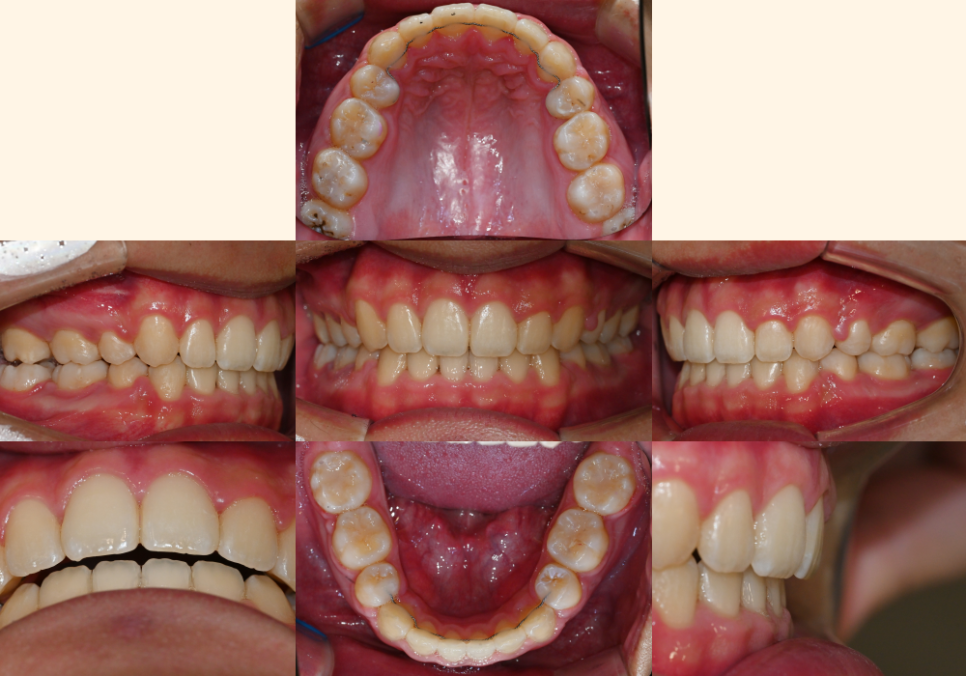

| 3. 종결 단계

25.06.12

매복되었던 치아는

완전히 정상 위치로 나와서

제 기능을 다하게 되었고,

사랑니도 성공적으로

어금니 자리에 정착하여

저작 기능을 담당하게 되었습니다.

특히 주변 치조골도 자연스럽게 재생되어

마치 원래부터 그 자리에 있었던 것처럼

건강한 상태를 보인다는 거예요.

절단연 교합은 완전히 개선되어

윗니가 아랫니를 적절히 덮는

정상적인 교합 관계가 확립되었고,

정중선도 완벽하게 일치하여

기능적으로나 심미적으로나

만족스러운 결과를 얻었습니다.